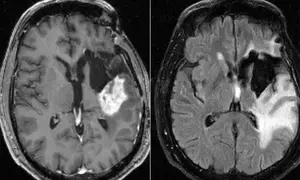

Potent immune cells found near glioblastomas, a possible cure